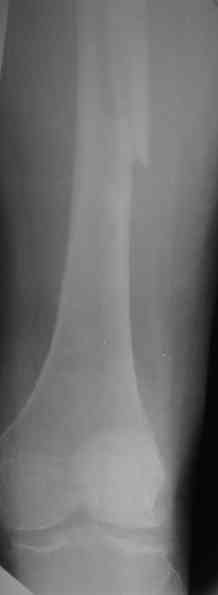

Уважаемые участники форума, просьба высказать Ваши мнения по представленному случаю. На прошлой неделе пациентке 74 лет, было выполнено цементное эндопротезирование тазобедренного сустава по поводу перелома шейки бедра.

Активизирована на следующий день, ходила с костылями, нагрузка полная. Дело близилось к выписке, когда она, поскользнувшись, упала в палате и получила то, что видите на снимках.Что бы Вы стали делать в подобной ситуации? Заранее спасибо.

A female 74 y.o. fell at day 7th after cemented THA. The femur is split from the tip of the troch (preexisted crack?) and fracture goes below the tip of the stem. Images attached. What type the fracture is according to Vancouver classification? We consider some kind of plating. What type of implant would you prefer? How long the plate should be? Is cable technique necessary? Grafting? Any probable pitfalls to concern? THX!